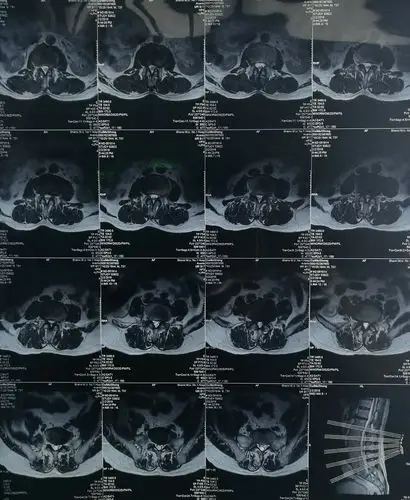

椎间孔镜治疗腰椎间盘极外侧突出一例的分享